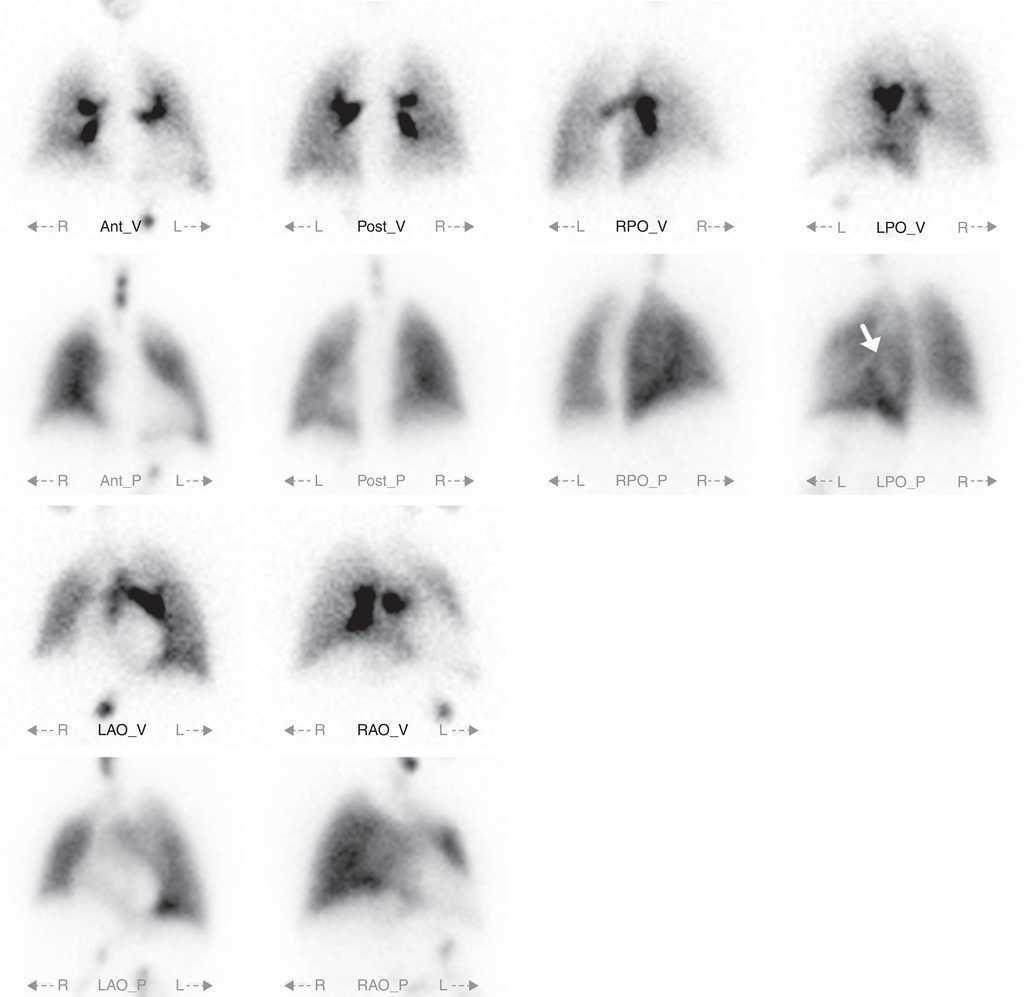

Figure 3, Figure 4, Figure 5 illustrate V/QS-SPECT larger sensitivity to detect perfusion defects. These examples demonstrate how, in one patient, V/QS-planar fails to correctly identify important perfusion defects, therefore failing to diagnose PTE, while V/QS-SPECT accurately documents them

Figure 3. V/QS-planar study; there is some heterogeneity in the perfusion of the left lung's lower lobe (white arrow), however it does not fulfil PTE diagnostic criteria and was disregarded as such.